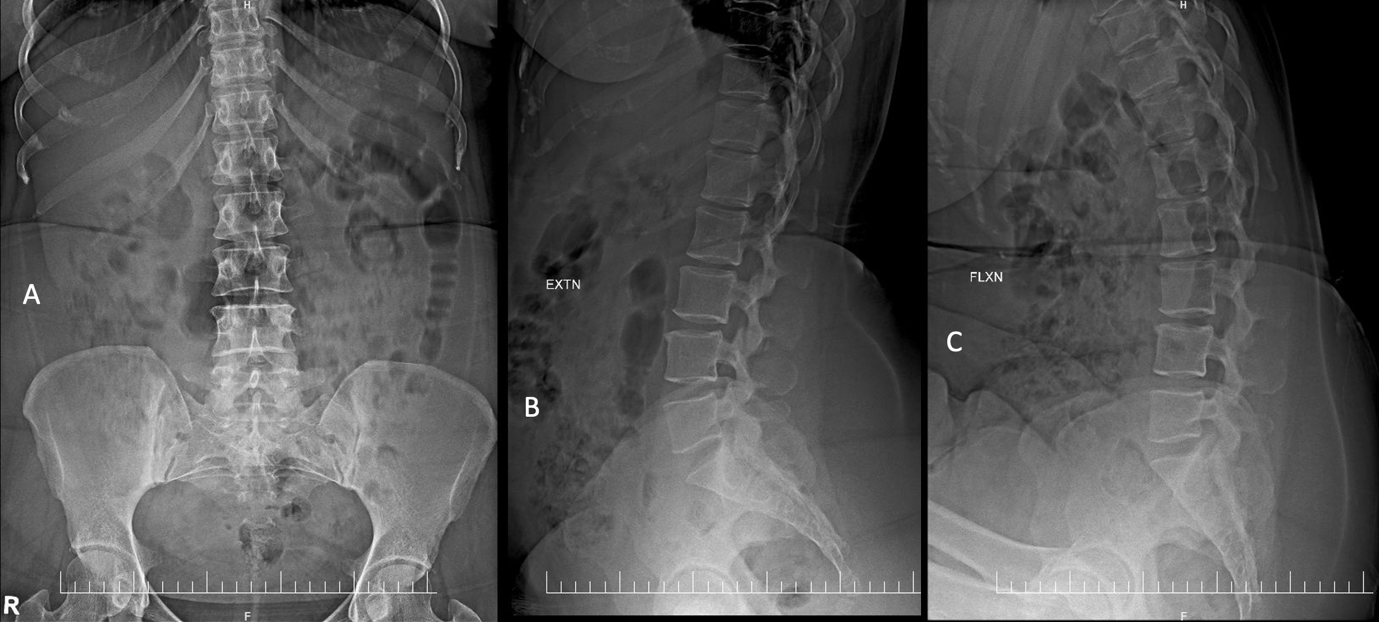

A 31-year-old nulliparous female presented with a 1-year history of sharp, burning pain localized to the right vulvar region, radiating to the perianal area and posterior thigh. The pain was spontaneous in onset, exacerbated by sitting and prolonged standing and significantly interfered with her daily routine, particularly her ability to engage in sexual activity. There was no history of recent trauma, infection or dermatologic lesions. Multiple prior therapeutic trials, including antifungals, topical steroids, tricyclic antidepressants and Gabapentinoids, offered minimal relief. On clinical examination, the vulvar skin appeared normal, without signs of inflammation or dermatologic pathology. Digital rectal examination revealed localized tenderness over the right ischial spine, suggestive of pudendal nerve irritation. There was no evidence of pelvic organ prolapse, perianal anesthesia or anal sphincter laxity. Her pelvic floor distress inventory-20 (PFDI-20) score was 7.13/300, consistent with minimal distress at presentation. The radiographs were unremarkable (Fig. 1). MRI of the lumbo-sacral spine, including T1-weighted, T2-weighted and short tau inversion recovery sequences, revealed a well-defined perineural (Tarlov) cyst measuring 1.7 × 1.2 × 1.3 cm at the right S2 neural foramen, with displacement and compression of the adjacent S2 nerve root. Mild disc bulges were also noted at L2-L3 and L3-L4 levels (Fig. 2). The lesion was classified as a Type II perineural cyst per Nabor’s classification and no other spinal abnormalities were detected. A diagnosis of neurogenic vulvodynia secondary to S2 nerve root irritation from the Tarlov cyst was established.

Figure 1: Radiographs of the lumbosacral spine in (a) anteroposterior and lateral extension (b) and flexion (c) views.